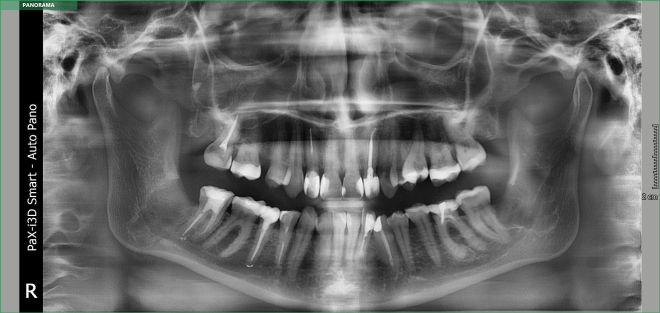

• Діагностика. 6 діагнозів.

• Класифікації за рівнем складності

• Техніки видалення зубів особливості планування від розрізу до останнього шва